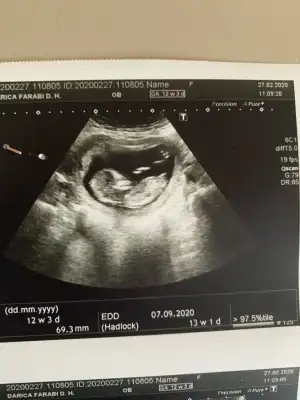

dr soylemeden siz gorun genital nub teorisi ( bebegin cinsiyeti)

Senin nubu çizdim cnm arkadaşında çizdim pipide vardı arkadaş pipi olsa söylemezmi deyince bende diğer 10 ve 11 haftasndaki tahminim devam dedim çok istiyordu pipiyi dr görmedi deyince ne kadar geç ögrenise dedim yoksa baya baya pipiydi çizdiğim usg 😊 seninkinide çizdim parelel görünüyor tabi pozisyonu nubu bazen değiştiyor. umarım 31 yanlış tahminim var arasında olmazsın onlar beni yanıtan usgler 😊

teşekkürler doktor erkek gibi ama emin değilim dedi 1 ay sonra kontrol inş. geri dönüş yapacağım iyi akşamlar.